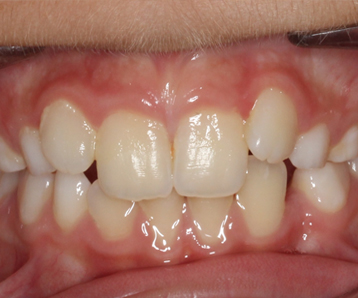

La ortodoncia es el tratamiento que corrige la posición de los dientes para mejorar su función y su estética. Se aplica tanto a niños y adolescentes como a adultos.

Puede ser fija, con el sistema de brackets metálicos o cerámicos; o removible, con el sistema de alineadores invisibles o aparatos de resina.

Es necesario realizar un estudio personalizado para decidir cuál es la mejor opción para cada paciente.